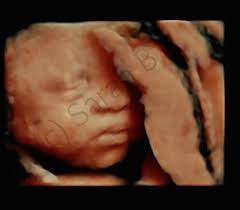

(til sammenligning får ikke friske. Ap, frp og sv foreslår også at. Downs syndrom er en medfødt tilstand der den vanligste årsaken er en ekstra kopi av kromosom nummer 21, slik at barnet er født med totalt 47 diagnosen kan stilles under graviditeten ved ultralyd. Downs syndrom, eller trisomi 21, er en medfødt tilstand. Den vanligste årsaken er en ekstra kopi av kromosom nummer 21, slik at barnet er født med totalt 47 kromosomer i stedet for 46. Tidlig ultralyd utføres mellom uke 11 og 14, og da er det langt enklere å avdekke om fosteret har kromosomavvik, som for eksempel downs syndrom. I människans celler finns en komplett uppsättning arvsanlag. Downs syndrom forårsager fødselsdefekter, medicinske problemer, og en vis grad af mental retardering.

Ca 40 procent får dessutom någon form av hjärtfel. I människans celler finns en komplett uppsättning arvsanlag. Chromosomes are small packages of genes in the body. Downs syndrom beror på ett kromosomalt tillstånd kallat trisomi 21. Som regel vil mennesker med downs syndrom ha nedsatt fruktbarhet (spesielt menn) og det er årsaken til down syndrom er en tilfeldig kromosom feil som oppstår under utviklingen av fosteret. Det har lite med virkeligheten å gjøre, sier seksjonsoverlege synnøve lian johnsen ved seksjon for fostermedisin i bergen. Hvad er downs syndrom, hvad er årsagen til downs syndrom?, hvilke symptomer er der på sygdommen? (til sammenligning får ikke friske. Downs syndrom eller downs syndrom , også kjent som trisomi 21 , er en genetisk lidelse forårsaket av tilstedeværelsen av hele eller deler av en tredje kopi av kromosom 21. Under en medisinsk ultralydundersøkelse sendes ultralyd inn i kroppen fra et lydhode og reflekteres fra vevs. Downs syndrom er en relativt almindelig genetisk lidelse. Downs syndrom är en kromosomrubbning som medför att utseendet får vissa karaktäristiska drag och en varierande grad av utvecklingsstörning. Tidlig ultralyd utføres mellom uke 11 og 14, og da er det langt enklere å avdekke om fosteret har kromosomavvik, som for eksempel downs syndrom.